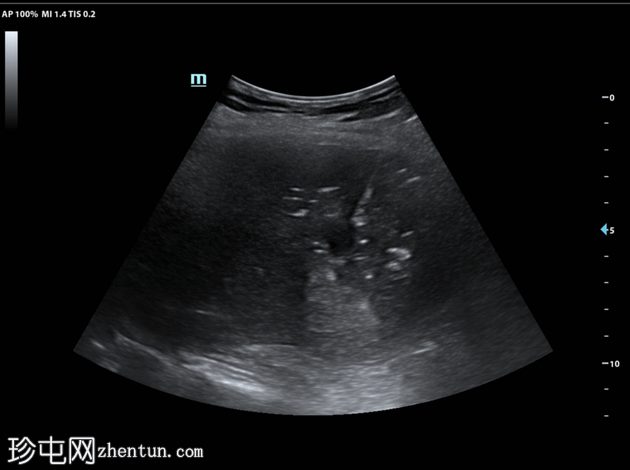

冠状位增强(C+)门静脉期

静脉期

7.jpg

肝段 6 和 7 可见多房性积液,呈环状强化

积液内可见多个气体腔

破入肝包膜下间隙,可见肝包膜下积液及气体腔

壁层腹膜与前腹壁之间可见另一局灶性积液

肝段 7 的肝内胆管局灶性扩张(0.3cm),内含气体腔

其他肝内胆管和肝外胆管均正常

胆囊缺失,可能由于既往胆囊切除术所致

无游离液体。

双侧肾皮质囊肿

轻度右侧胸腔积液伴邻近肺不张